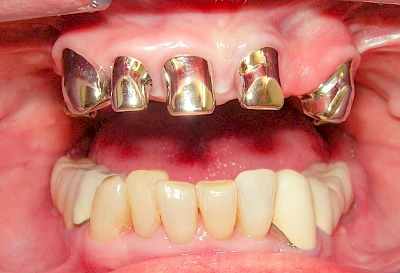

Implantate: Kronen & Brücken

Fehlen einzelne Zähne und die Nachbarzähne sind unbeschadet oder gut zahnärztlich versorgt, werden immer häufiger Implantate gewählt, um die Lücken zu schließen. Auch bei größeren oder verteilten Lücken, wenn keine herausnehmbare Prothese gewünscht ist, werden Implantate für Kronen- bzw. Brückenversorgungen gesetzt. In Einzelfällen entscheiden sich sogar zahnlose Patienten für eine festsitzende Versorgung auf Implantaten.

Varianten zur Verankerung von festsitzendem Zahnersatz auf Implantaten